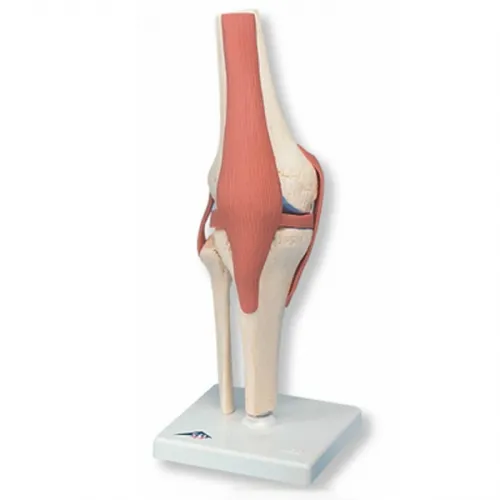

두 번째는 연골 손상

무릎 관절 사이에서 뼈와 뼈의 마찰을 줄여주는 부드러운 조직인 연골이 관련되어 있습니다. 나이 증가, 과체중, 관절염 등으로 인해 연골이 닳거나 소실되면, 뼈 사이의 직접적인 마찰로 인해 통증이 발생할 수 있으며, 이로 인해 움직임의 제한, 삐걱거리는 소리, 염증과 같은 증상이 나타날 수 있습니다.